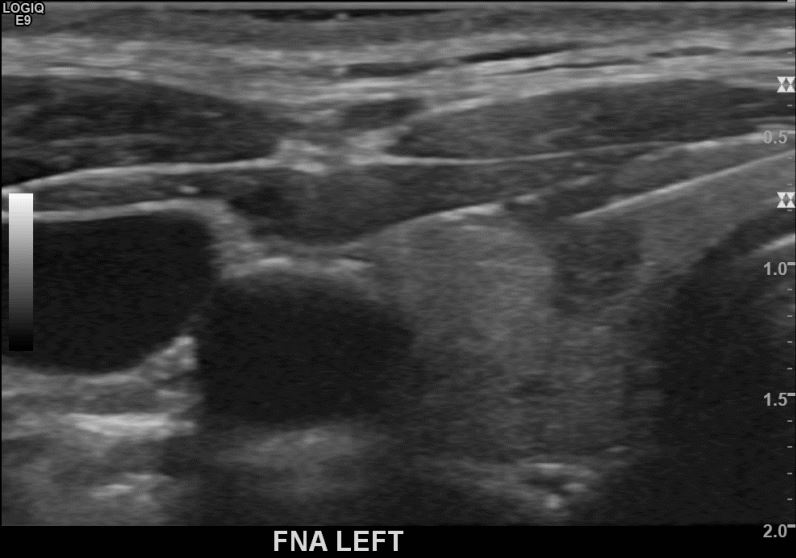

상기환자 외부검진이후 추적검사위해  내원하신 30대후반 여성분으로 의심스러운 좌엽혹 세포검사진행후 갑상선암으로 진단되었습니다